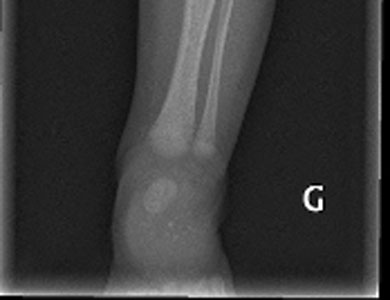

Врожденный порок развития средних отделов лица, характеризующийся плоским носом, втянутой субназальной областью (псевдопрегнией), укорочением альвеолярного отростка верхней челюсти, выпуклой верхней губой, атрофией слизистой оболочки носа без нарушения обоняния.

Рентгенологическая картина

Аплазия или гипоплазия костей носа, альвеолярного отростка верхней челюсти, лобных пазух.